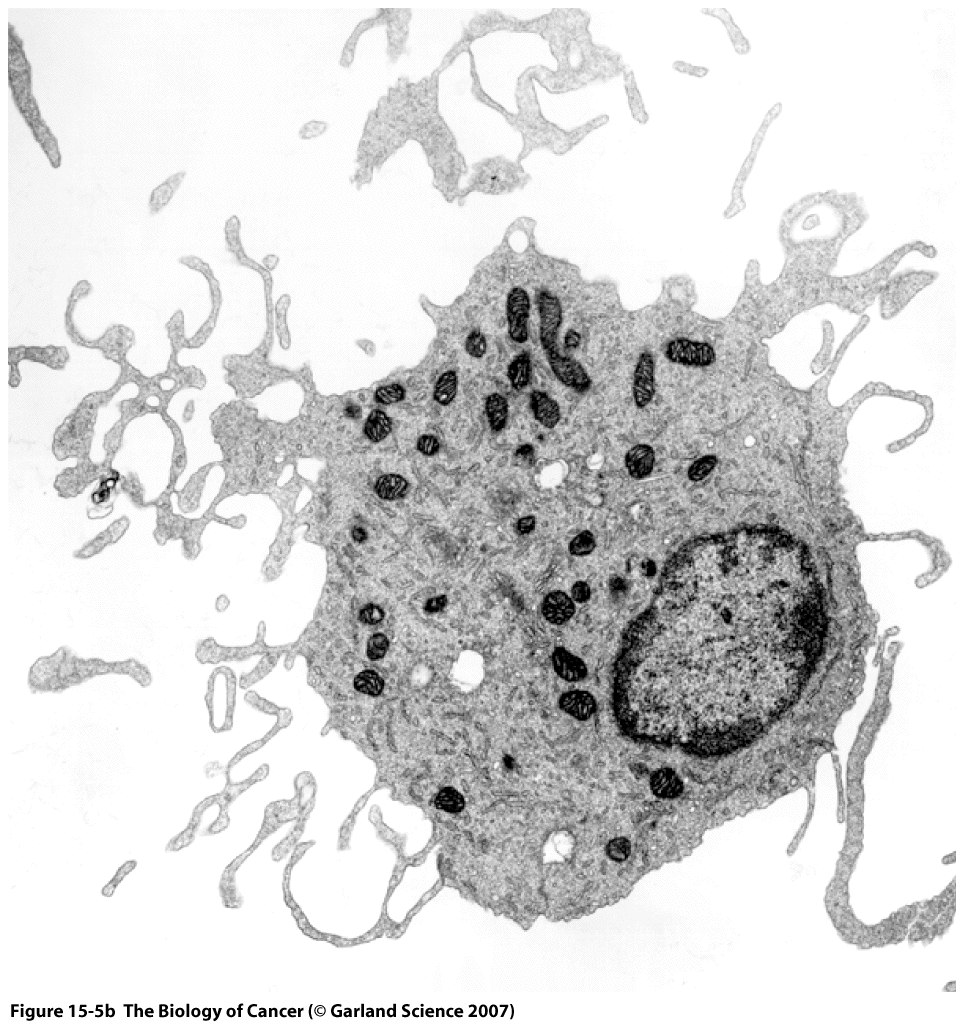

This Concept Map has information related to: Chapter 15 discussion Imunology, natural killer (NK) cells bind to potential target via NKG2D receptor, intrinsically resistant to forms of killing eg increased inhibitors, herceptin is humanized, cancer cells recruit normal cells, self reactive lmphocytes recognize sel-antigens, autoimmune attack induced by Antibody molecules, cytotoxic cells e.g. natural killer (NK) cells, intrinsically resistant to forms of killing eg stop complement formation on cell surface, Antibody molecules recognize and bind Antigens, major histocompatibility complex (MHC) class II molecules present Antigens